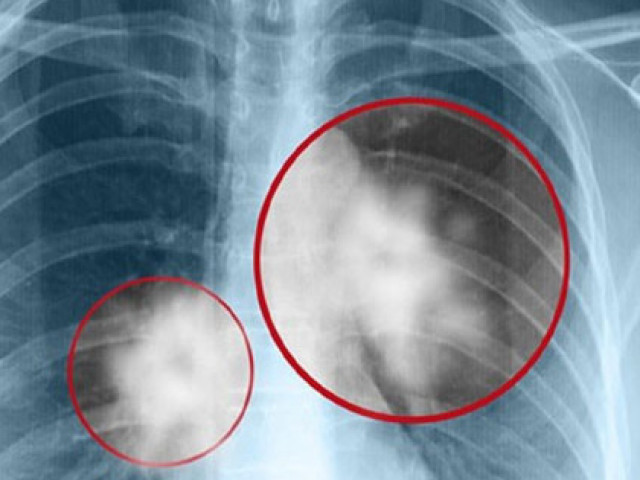

Ảnh minh họa: Internet